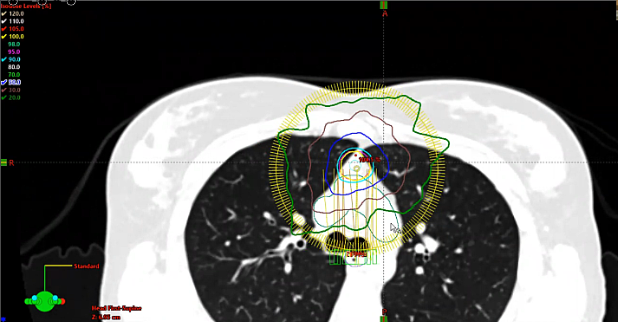

Lymphoma radiation, dose, local palliation, CTV

Follicular lymphoma, R-CHOP Chemotherapy, DLBCL, nodular lymphoma, post treatment scans, testicular lymphoma, photons vs. electrons, target volumes, dose, side effects, paranasal lymphoma, elderly, multiple myeloma, bone mets,